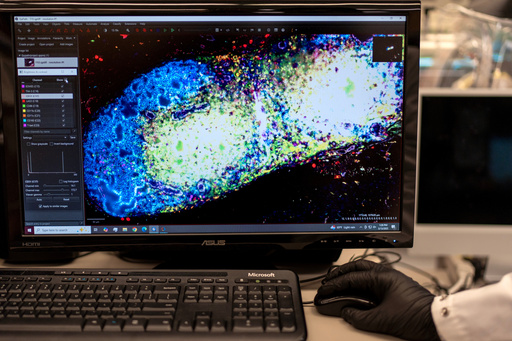

In Green's lab, a computer screen shines with brightly colored dots that resemble a galaxy. It’s a biological map that shows insulin-producing cells in the pancreas of a mouse. Red marks rogue T cells that destroy insulin production. Yellow indicates those peacemaker regulatory T cells — and they're outnumbered.

Green's team aims to use that mRNA to instruct certain immune “generals” to curb the bad T cells and send in more peacemakers. They package the mRNA in biodegradable nanoparticles that can be injected like a drug. When the right immune cells get the messages, the hope is they'd “divide, divide, divide and make a whole army of healthy cells that then help treat the disease," Green said.

The researchers will know it's working if that galaxy-like map shows less red and more yellow. Studies in people are still a few years away.